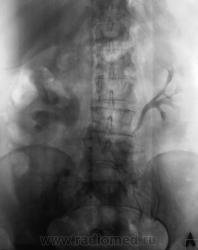

5.Округлый дефект выполнения в области устья правого мочеточника вполне может быть обьяснен наличием уретероцеле, а тогда станет понятна и причина камнеобразования справа.

Фрагмент с мочевым пузырем.

Пока все сходится, осталось только уточнить природу этого самого дефекта выполнения...что, все таки, говорят по этому поводу УЗИсты?

Не могли бы вы ткнуть в него пальцем?

Сегодня говорил с коллегой - пациентной.

Да, камень в мочеточнике, гидронефроз, почка удалена.

В мочевом пузыре - доброкачественная опухоль.